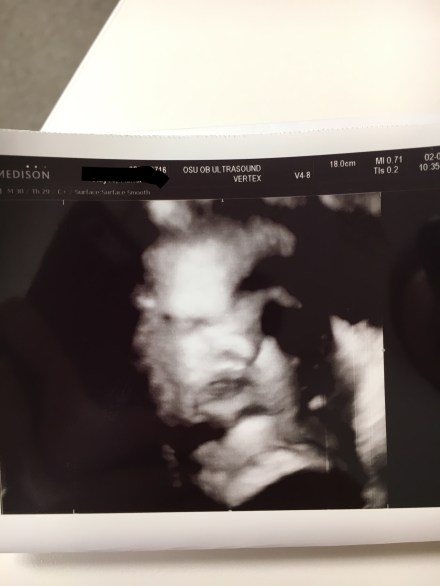

Now for some pictures.

A 3D view of her looking straight at us. One eye, nose and lips are shown here.